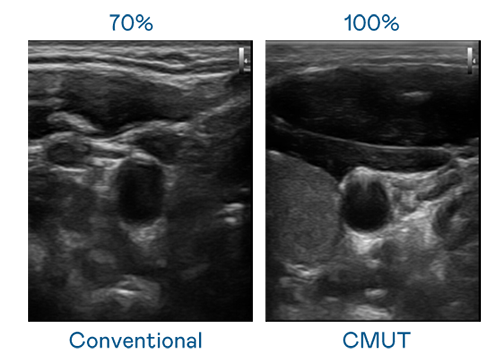

CMUT 技术是一种用电容式微机电元件来产生超音波讯号的技术。与传统 PZT 压电式技术相比,CMUT 频宽增加 30%,更宽频的超音波讯号让影像解析度大幅提升,是实现高影像品质医疗超音波扫描、促进精准医疗发展的关键技术。

大频宽带来超清晰影像

超音波影像的解析度高低,首先取决于探头能发出的讯号频宽。一个好妈妈2韩剧蘑菇 CMUT 可提供高清晰的超音波讯号,提供高频宽、高灵敏度、影像纹理细节更高的超音波影像,协助医护人员缩短影像判读时间及利用精准的医疗影像进行诊断。